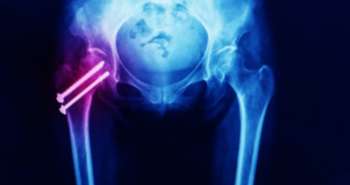

Obese people exhibit a prodigious bidirectional connection with single-site and widespread joint pain.

A total of fourteen studies which exhibited significant cross-sectional relationship (SMD 0.49) of widespread pain with total body fat mass were involved in the meta-analyses (p < 0.001). Higher body fat percentage was seen among persons having knee (SMD 0.18) and low back pain (SMD 0.34). Foot pain also showed a weak (SMD 0.05) but significant relationship with fat mass index (p < 0.001). A total of 8 longitudinal studies assessed were unsuitable for meta-analyses but provide considerable evidence of high body fat relations with increased and worse joint pain risk. The evidence found of low back pain and body fat associations in the follow up of 4 to 20 years were showed specific conflicts. However, the positive relationship was seen in body fat percentage and fat mass index with increased foot and knee pain incidences. The variable methodological quality of involved studies was evaluated through EAI grade as 'yes' for each study ranged from 23 to 85%.

The single-site and widespread foot, knee and low back joint pain shows a positive correlation with increased body fat. As per results, raised body fat relates with elevated worsening of pain. More high-quality studies are needed for further evaluation.